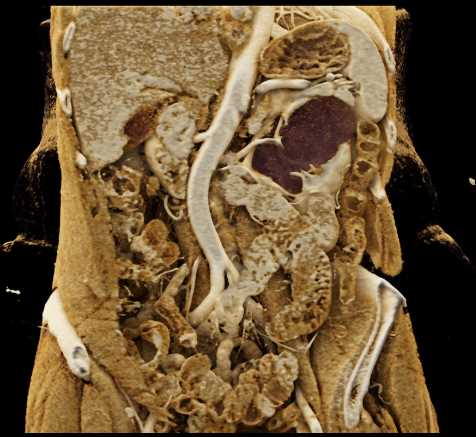

Acute Pyelonephritis Right Kidney